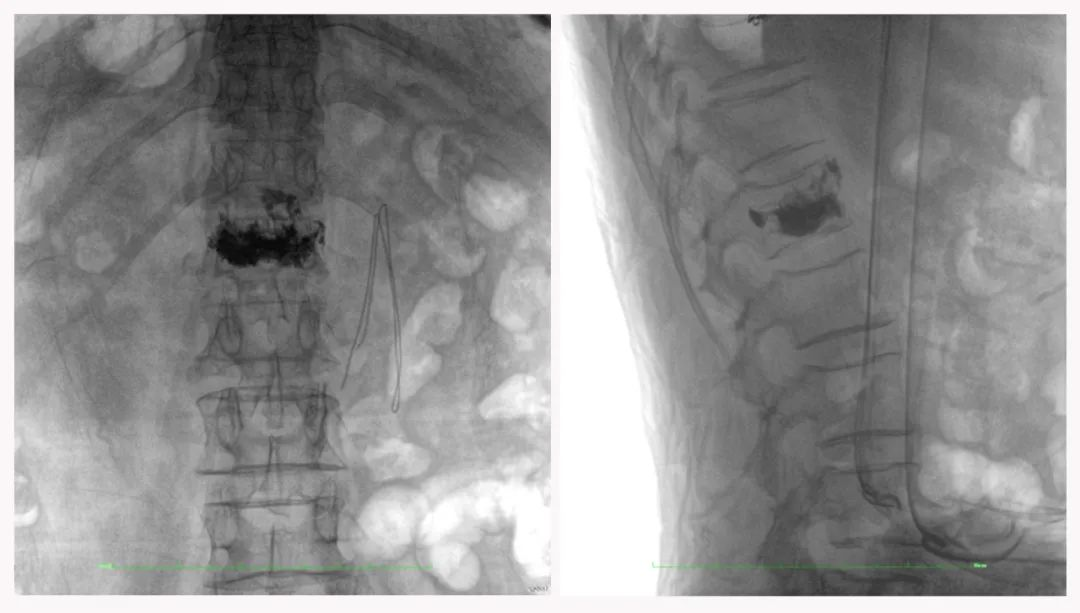

二維正側(cè)位影像

三維“類CT”影像

病例1:右側(cè)股骨遠端骨骺骨病(13歲)

二維影像看不到病灶點

三維切面影像可以看出病灶點